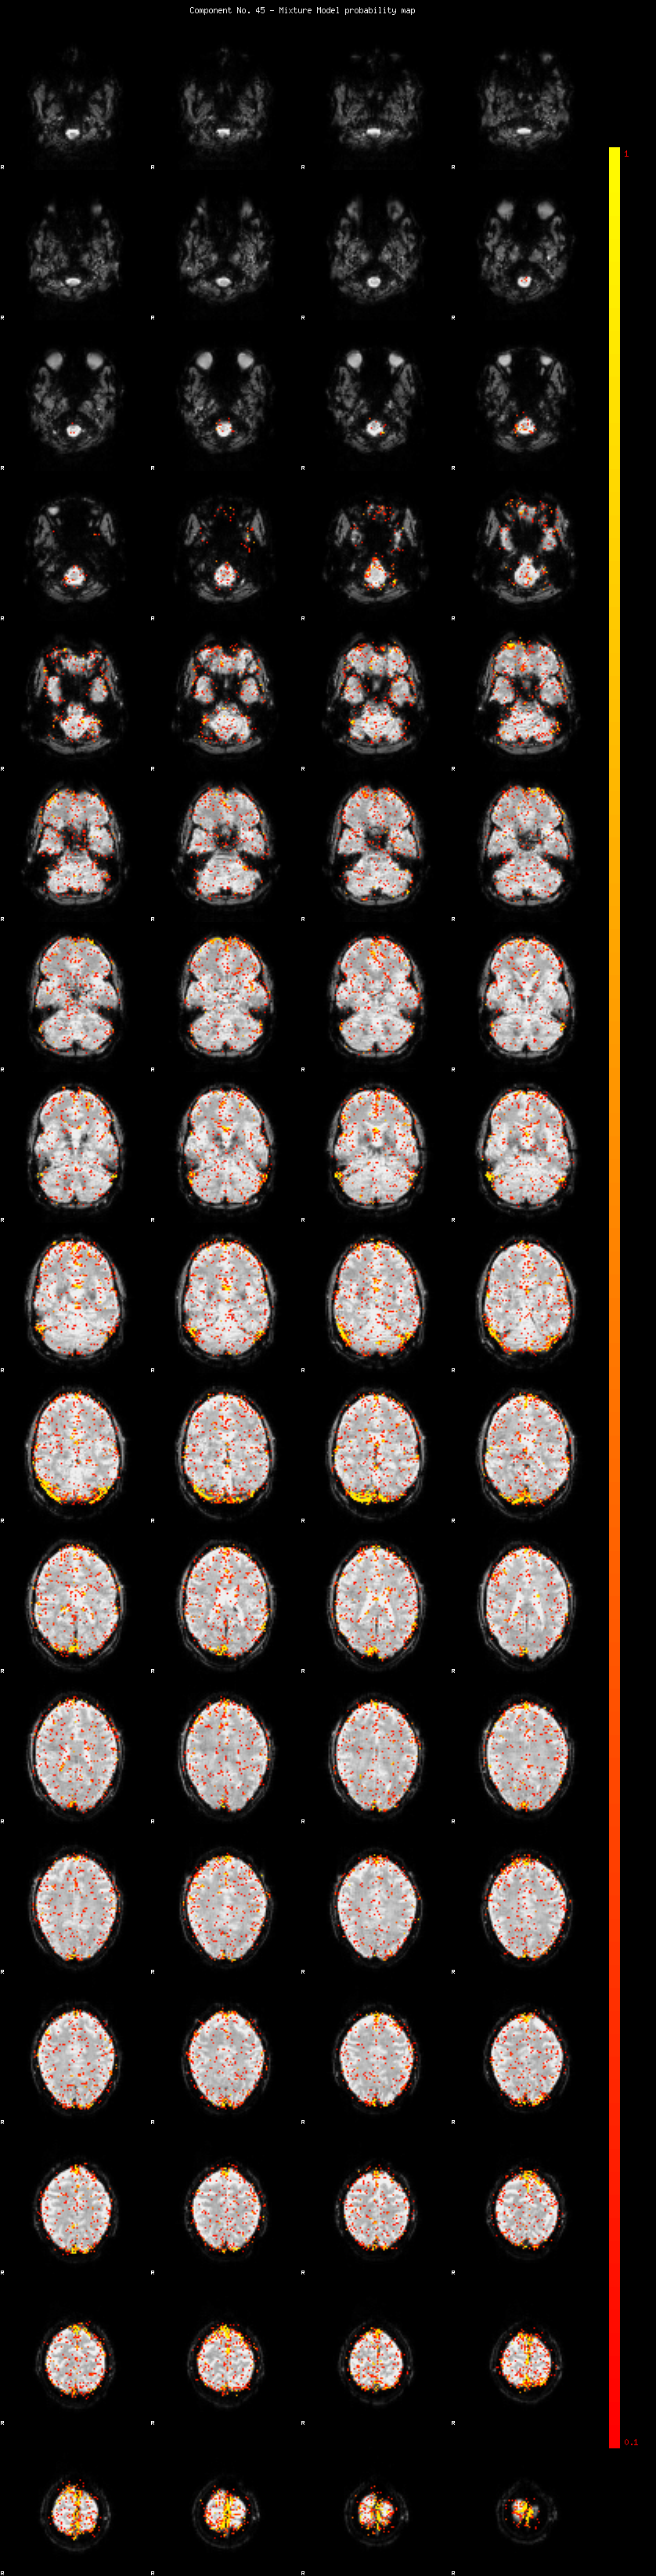

IC_45 Mixture Model fit

Means : -0.000000 2.717844 -2.404956

Vars : 1.000000 2.839340 1.340366

Prop. : 0.944595 0.034782 0.020623